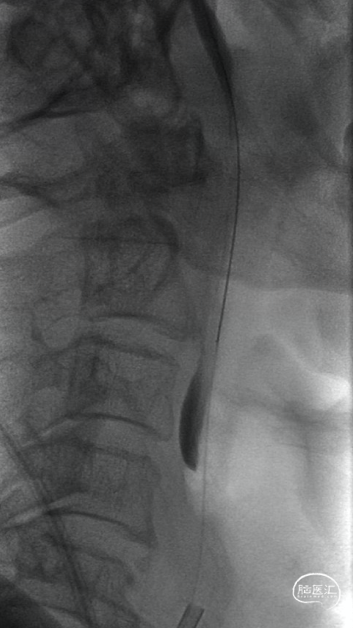

交换出微导管及多功能导管,C2段放置SPIDER保护伞后以3-30mm球囊和6F 115cm SKATHI远端通路导管采用球囊接力技术越过颈内动脉闭塞段,由下及上持续抽吸。

回撤SKATHI远端通路导管至C3段,通过导管再次释放SPIDER保护伞,回撤导管至颈总动脉,造影见C1段严重狭窄,以4-30mm球囊扩张狭窄段,复查造影狭窄段好转,远端再次闭塞,考虑斑块或血栓脱落,立即置入7-40 wallstent支架。

3. 对于串联病变中来讲,越过闭塞段抵达颈内动脉远端是第一步,像本例患者由于缺乏着力点并且C1段斑块较硬,微导管微导丝难以奏效。利用多功能管的头部弯曲对准闭塞段,采取较硬的微导丝如Command或者PT能有效突破闭塞段,在跟进中间导管时采用球囊接力技术不但可以轻松越过闭塞段,而且可以防止损伤中间导管(或抽吸导管)头端,避免头端损伤后抽吸能力下降。